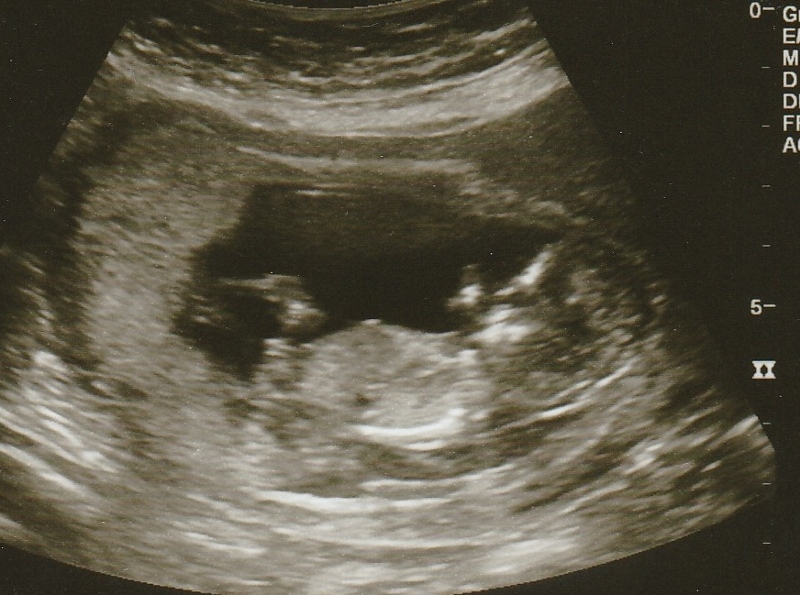

12w3d Nub guess anyone?

Hi! I had my first scan today at 12w3d and baby was measuring just a couple days ahead. Any guesses based on the nub? Thanks!! I am not sure that these all havve a clear nub but thought i'd add them just in case.

Bumping to see if anyone has anymore guesses. Going to get an elective scan tomorrow. I'm only right at 15 weeks so I don't know if it will be accurate but im hoping to see obvious boy bits!! Lol